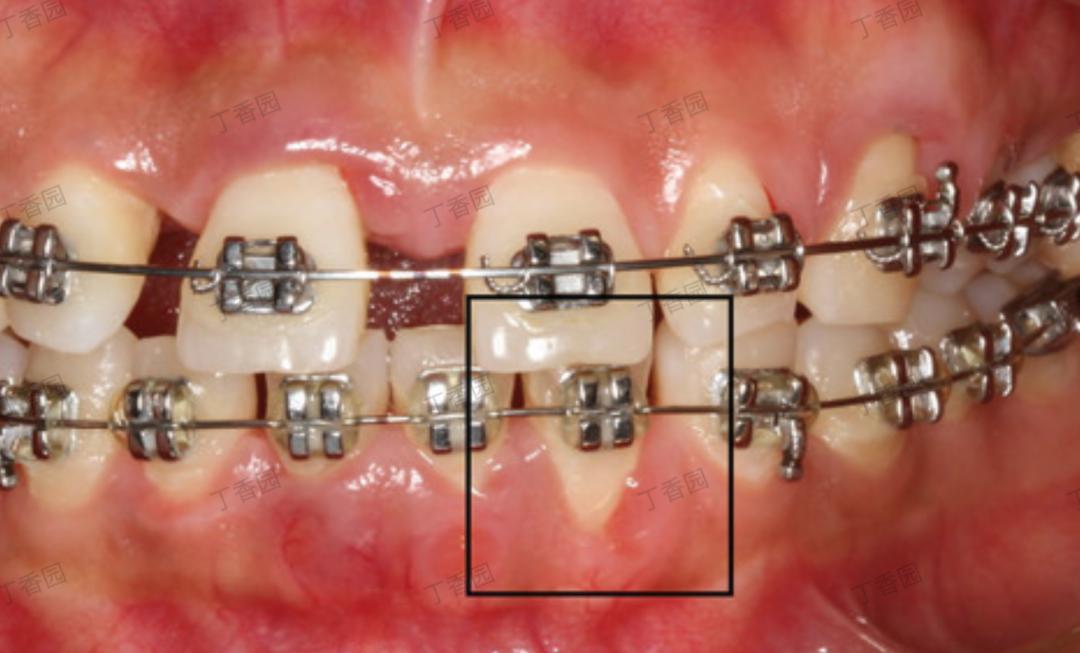

不良修復體或正畸過程中拉太快:也可能產生壓迫或刺激12]

正畸牙移動與牙齦退縮

圖片來源:丁香園